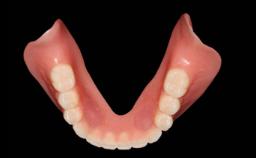

A 93-year-old female patient presented in September 2010 with an enlarged swelling on the lingual side of her lower incisors. At the time, she was essentially healthy, except for reduced vision due to bilateral age-related macular degeneration. She had been a heavy smoker (about 30 cigarettes a day) for the past 20 years after becoming a widow. The patient lived at home by herself, with full-time domestic support. An extraoral examination revealed nothing adverse. Intraoral plaque control was anything but ideal, and a soft-tissue tumescence was visible around the lingual aspect of 41–42. Because the nature of the lesion was not clear, a biopsy was carried out that revealed the inflammatory nature of the lesion. The panoramic radiograph showed six irregularly distributed mandibular implants supporting a full-arch prosthesis, with various degrees of interproximal peri-implant resorption. The periapical radiograph revealed interproximal bone resorption mesially and distally to implant 41.

# of Implants 2

Type of Implants One-Piece

Attachment One-Piece

Prosthesis Type FDP